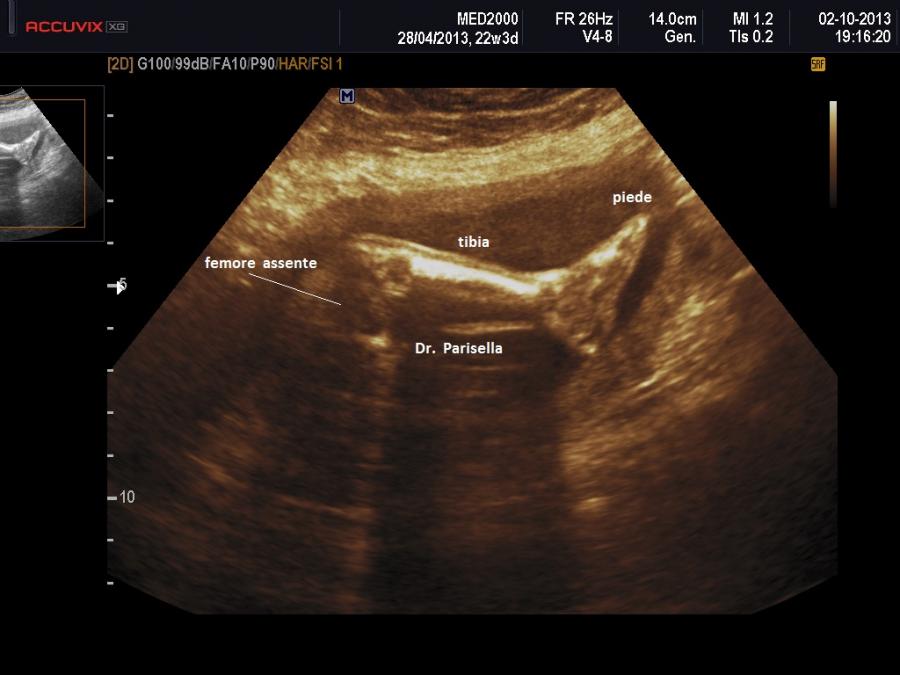

Per quanto riguarda il primo punto lo studio deve comprendere in modo dettagliato tutti e quattro gli arti e/o i loro segmenti: tratto rizomelico (femore-omero), tratto mesomelico ( tibia-perone ; radio-ulna), tratto acromelico (mano-piede) e la unilateralità o bilateralità.

L'Emimelia è un difetto che interessa i segmenti mesomelico e acromelico. Può essere classificata in due tipi: 1) longitudinale quando a mancare è il raggio osseo mediale o laterale di un arto, cioè manca uno tra radio e ulna o uno tra tibia e perone; di solito radio e perone sono i più colpiti; nell'emimelia radiale si associa una mano torta; 2) trasversale quando manca completamente la parte distale di un arto: in questi casi in genere è presente un moncone tipo amputazione.

Displasia Rizomelica: l'accorciamento interessa solo il femore e/o l'omero; spesso è associata a cromosomopatia.

Displasia Mesomelica: l'accorciamento interessa la tibia e/o il perone e/o il radio e/o l'ulna.